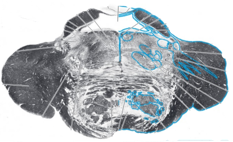

13

Q

Name this brainstem cross section:

A

Rostral Pons